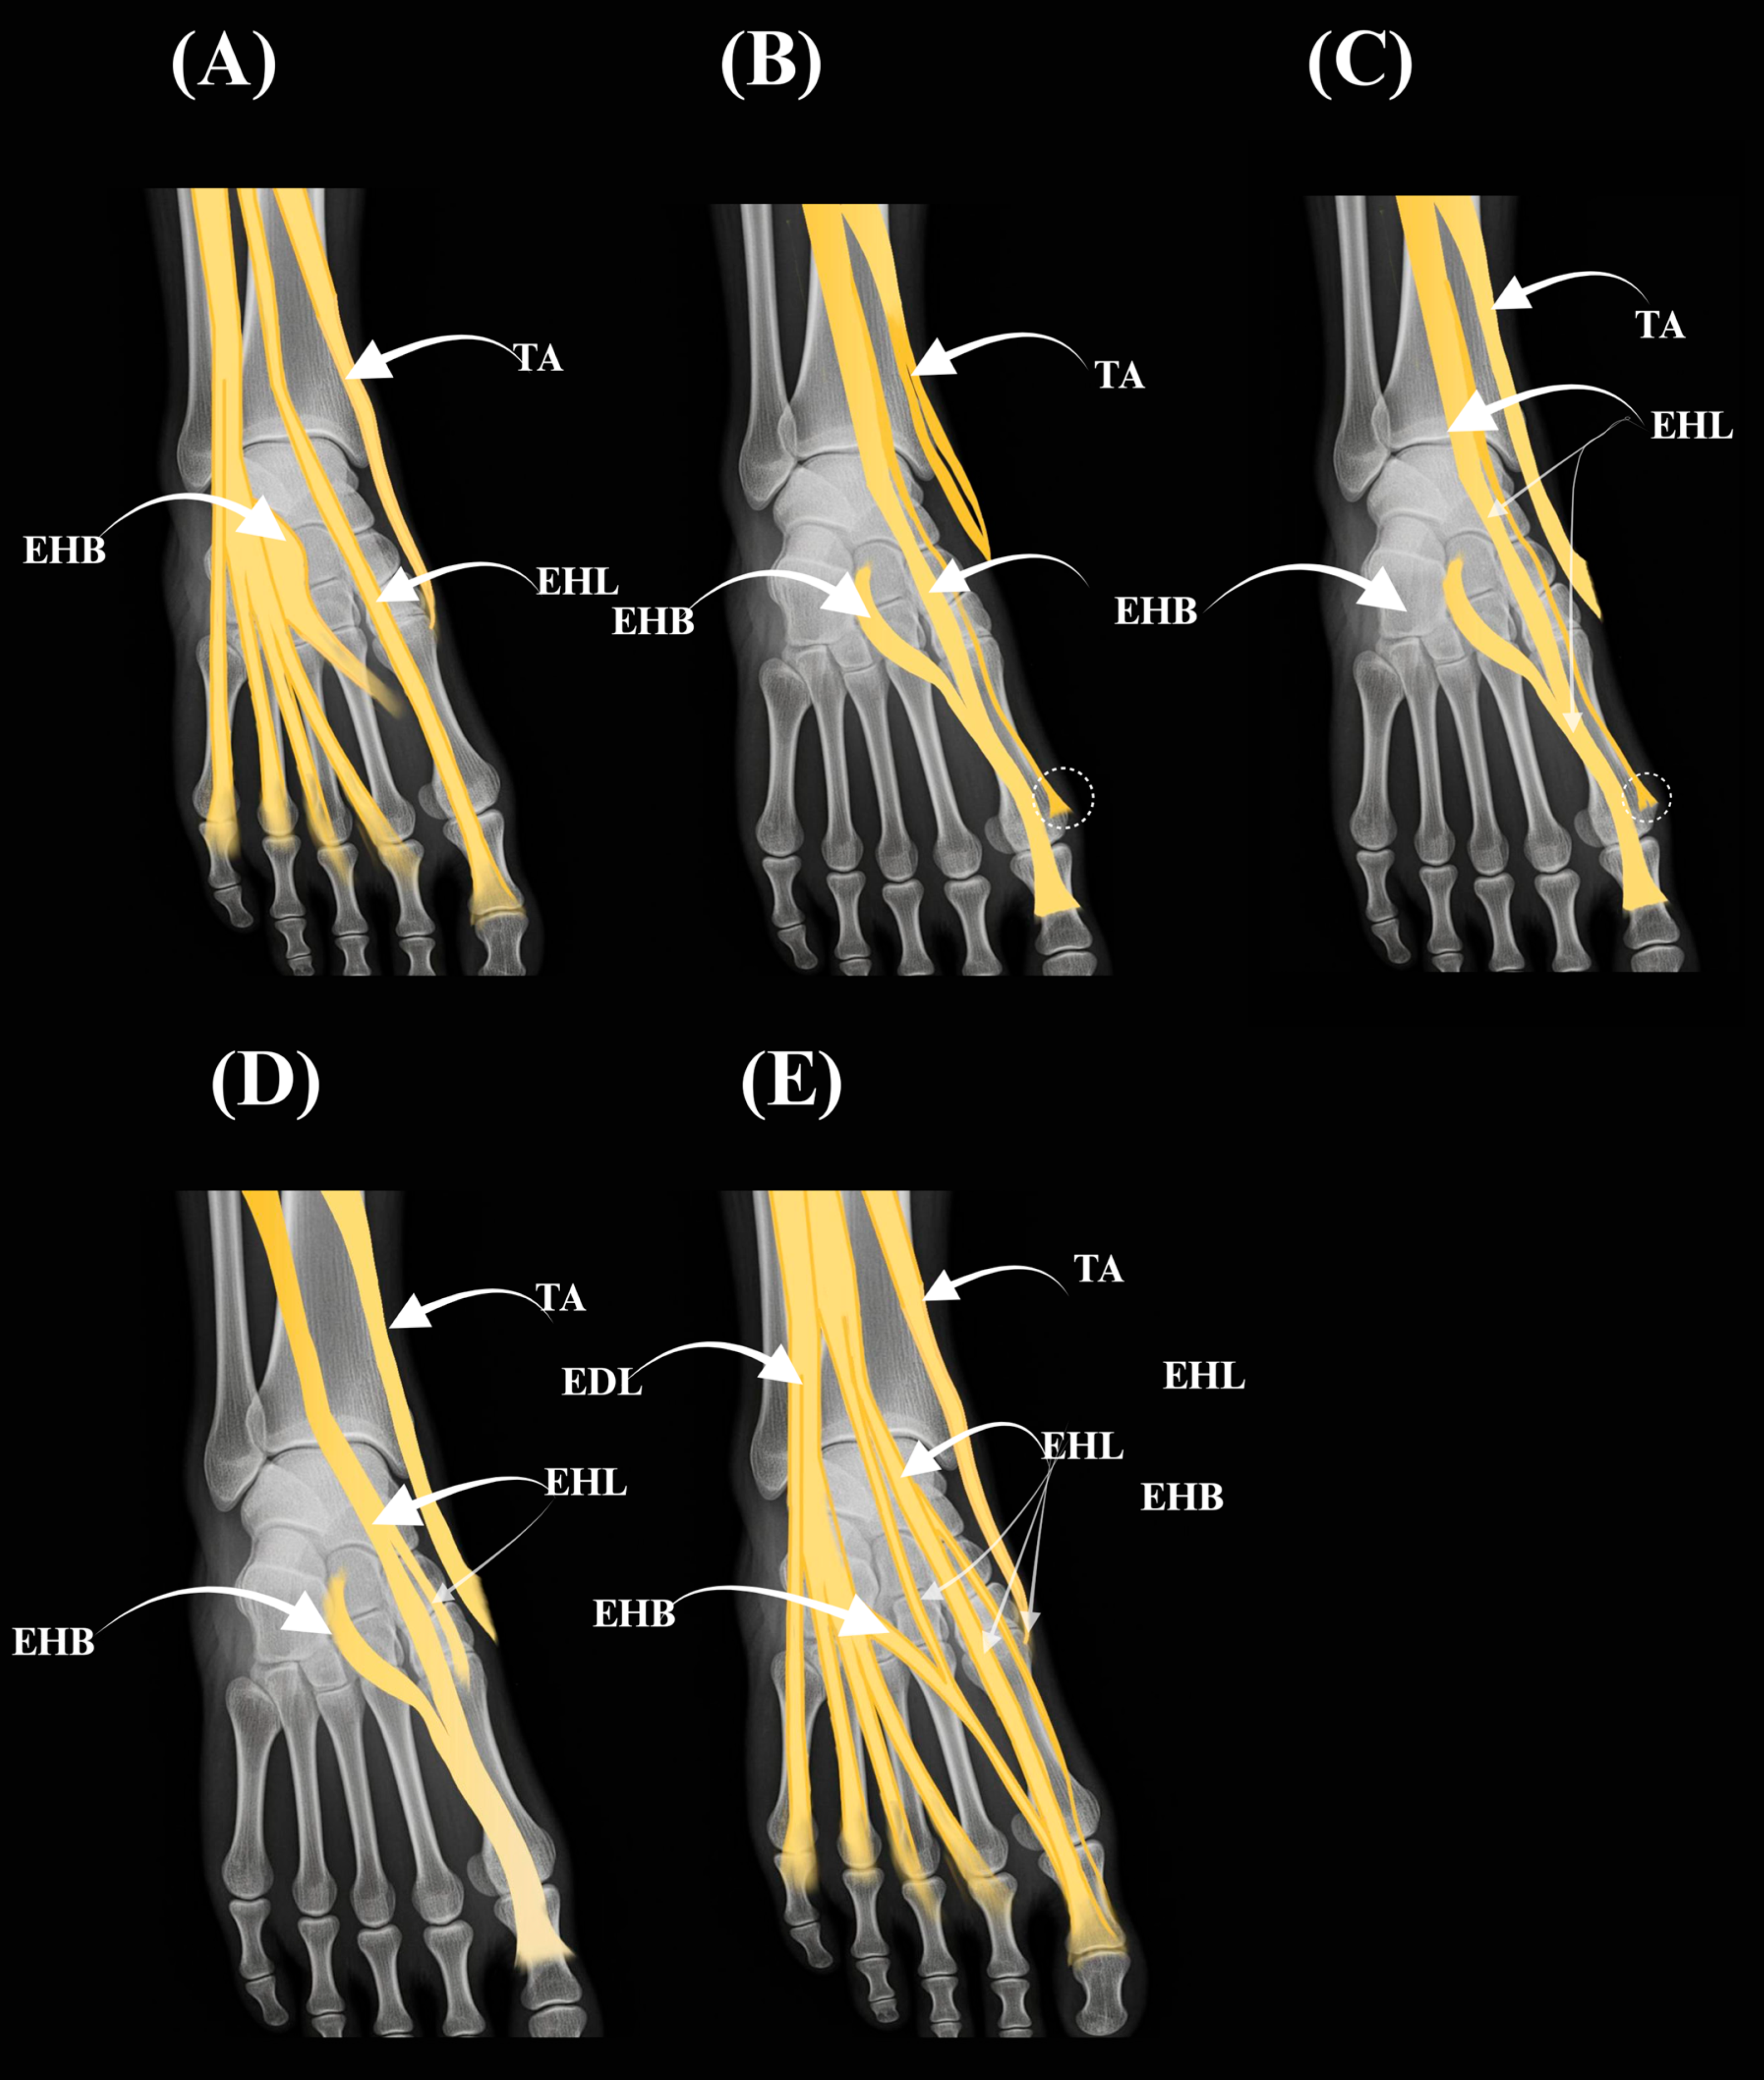

3.1. Type I—Classical Configuration

3.2. Type II—Two Tendinous Slips (Subtypes IIa–IIc)

3.2.1. Type IIa

3.2.2. Type IIb

3.2.3. Type IIc

3.3. Type III—Three Tendinous Slips